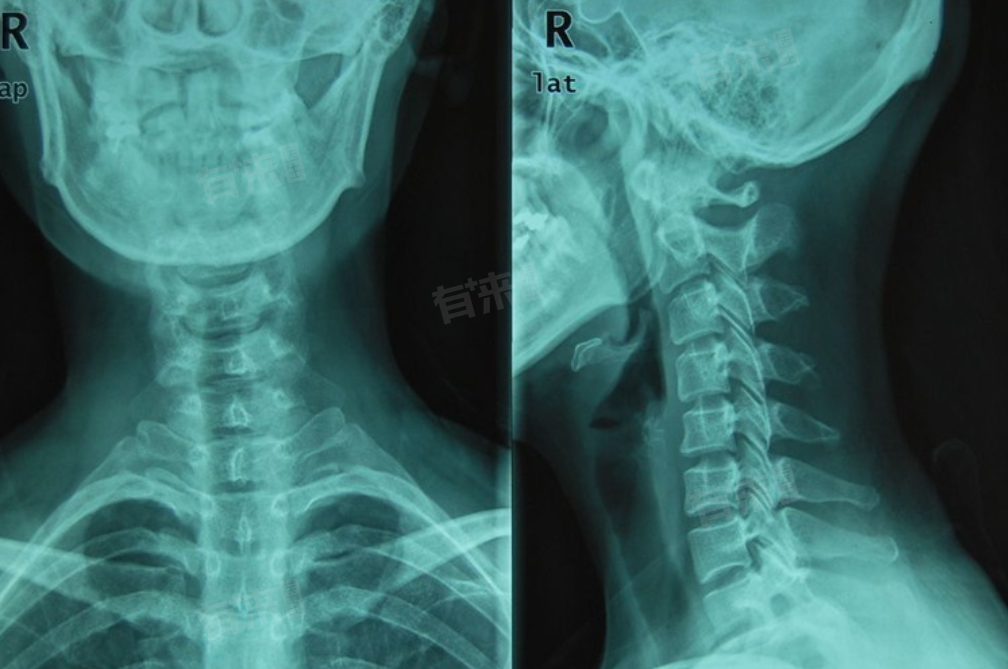

- 影像学检查至关重要,X线检查是基础项目,拍摄颈椎正侧位片,可清晰显示颈椎整体形态,直观观察颈椎生理曲度是否改变,有无反弓现象,还能查看椎体有无骨质增生、椎间隙是否狭窄等,为诊断提供重要依据。